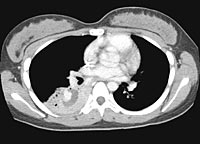

A repeat CT scan is seen below.

ENLARGE

this CT image.

WHAT

IS YOUR INTERPRETATION?